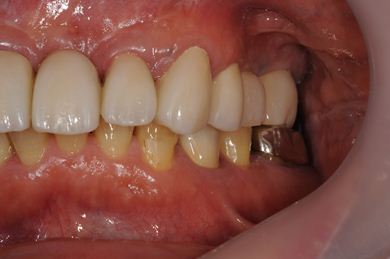

インプラントの症例写真 IMPLANT

骨再生インプラント治療

| 治療方針 | 右上奥はソケットリフトにて上顎洞拳上してインプラント埋入を可能にし、上顎前歯部は骨再生法によりインプラント治療を行う。その他、補綴により口腔内全体の機能的審美的回復を行う。 | ||||||||||||||||||||||||||||||||

| 治療内容 | インプラント8本(GBR、ソケットリフト)、ハイブリッドセラミッククラウン17本(セラミック用土台5本) | ||||||||||||||||||||||||||||||||